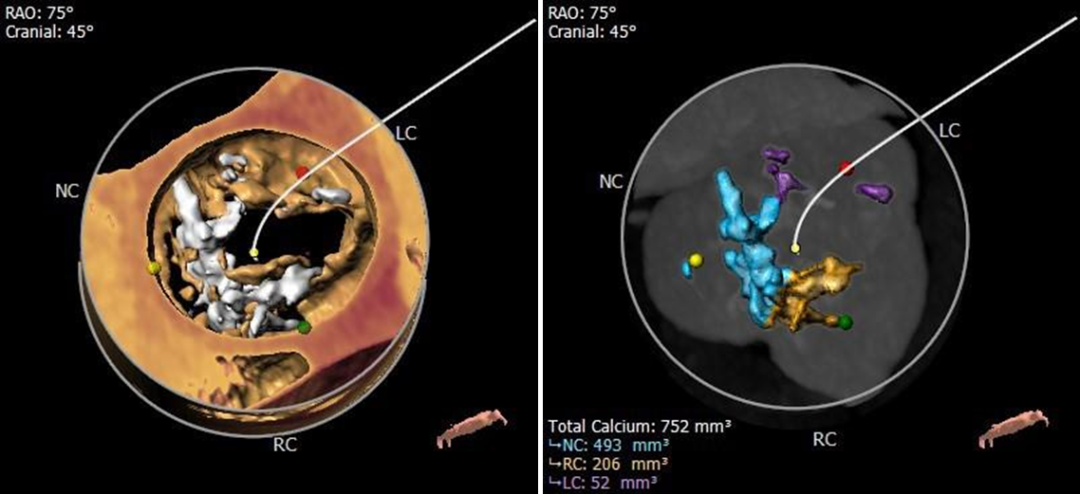

钙化分布

重度钙化,HU850 752mm³

CT动态预览

三窦式,瓣叶增厚,R-N钙化融合,L-N瓣叶粘连

根部测量

瓣环平均径25.4mm,瓦氏窦、STJ、升主内径可,非横位心

冠脉测量

冠脉开口高度可,切线位测量未见冗长瓣叶